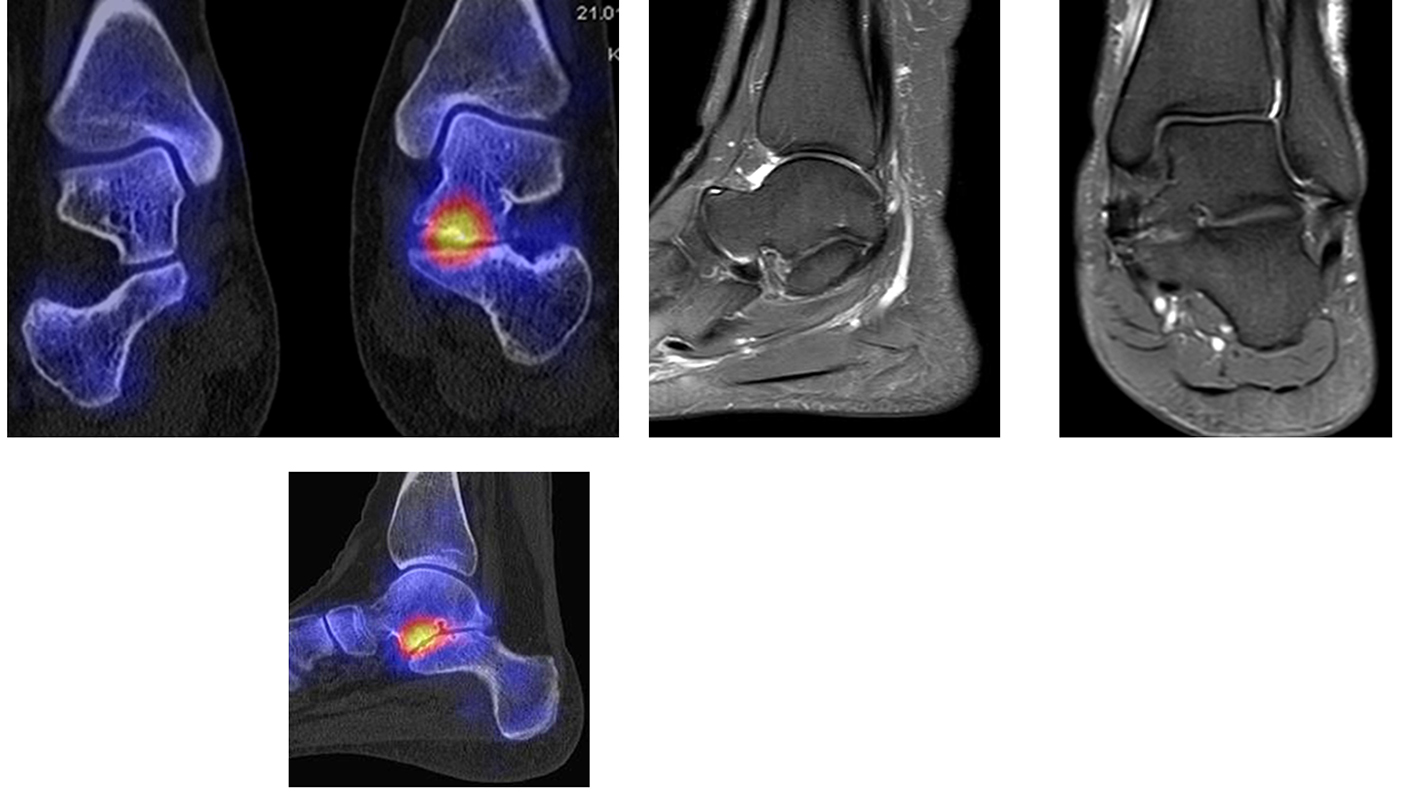

Osteonekrosen

Abbildung 9.2.a bis d: SPECT/CT zur Beurteilung der Knochen-Vitalität bei einer Talusnekrose. 5 Jahre zuvor während der Arbeit war die Patientin beim Treppensteigen umgeknickt und zog sich Außenbandrupturen zu. Nachfolgend persistierende Beschwerden mit Entwicklung einer Talusnekrose. Frage nach Vitalität und Ausdehnung der Nekrose. Deutliche bis intensive Traceranreicherung im Bereich des linken Talus. Im SPECT/CT befindet sich der Hypermetabolismus in allen Abschnitten des Talus mit relativer Aussparung eines sich demarkierenden Fragmentes lateral, was die laterale Talusschulter umfasst, die Größe beträgt transversal ca. 23 x 16 mm. In diesem Fragment relativ homogene Skelettstruktur, diese Befunde weisen auf eine trophische bzw. nekrotische Störung des Talus hin mit einem sich demarkierendem Fragment, welches die laterale Talusschulter beinhaltet.

Die Abbildung 9.3.a bis d zeigt ein weiteren Fall mit einer SPECT/CT zur Beurteilung der Knochen-Vitalität bei einer Talusnekrose. Die Bilder zeigen eine abgelaufene Nekrose mit zystischen Resorptionen des linken Talusdoms bei nachweislich erhaltener Vitalität der umgebenden Knochenabschnitte aufgrund des hier überall deutlich erhöhten Knochenmetabolismus (= inkomplette Restitutio). Aufgrund der nachweislich erhaltenen Vitalität konnte erfolgreich eine Knochen-Transplantation erfolgen.Deutlich geringer ausgeprägte nekrotische Veränderungen auch im rechten Talusdom bei hier weitgehend erhaltenen Gelenkkonturen.